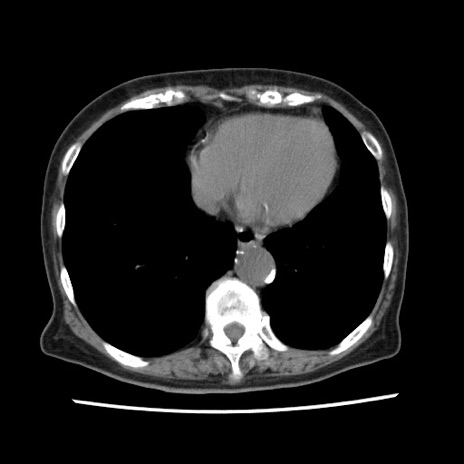

症例1(横断像)

【症例】80歳代女性

【主訴】腹痛

【現病歴】8時間前から腹痛あり来院。

【既往歴】糖尿病、脂質異常症、子宮体癌にて子宮全摘術

【身体所見】意識清明・会話良好だが腹痛で苦悶様、全腹部にわたって反跳痛と圧痛あり

【データ】WBC 13600、CRP 0.14、LDH 224、CK 90